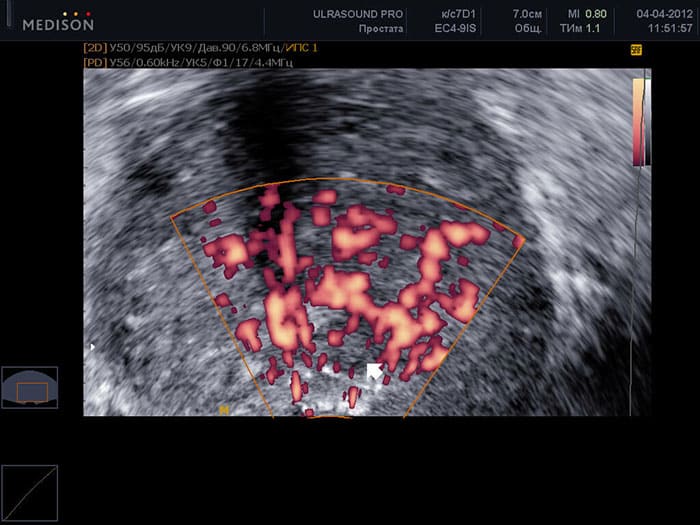

The mechanism is simple: without sex, blood supply to the pelvic organs decreases, problems with urination begin, and prostatitis develops. Problems in the early stages are hard to detect, and when they are detected, surgery is often necessary. Look at this image from the Institute of Urology:

Prostate cancer in a 48-year-old man. Prostate cancer is the most common cause of death (up to 88%) among men suffering from weak erections. It arises due to the lack of normal blood circulation in the pelvic organs and purulent stagnant phenomena in the prostate itself. This leads to cancer and inevitable death within 1-2 years.